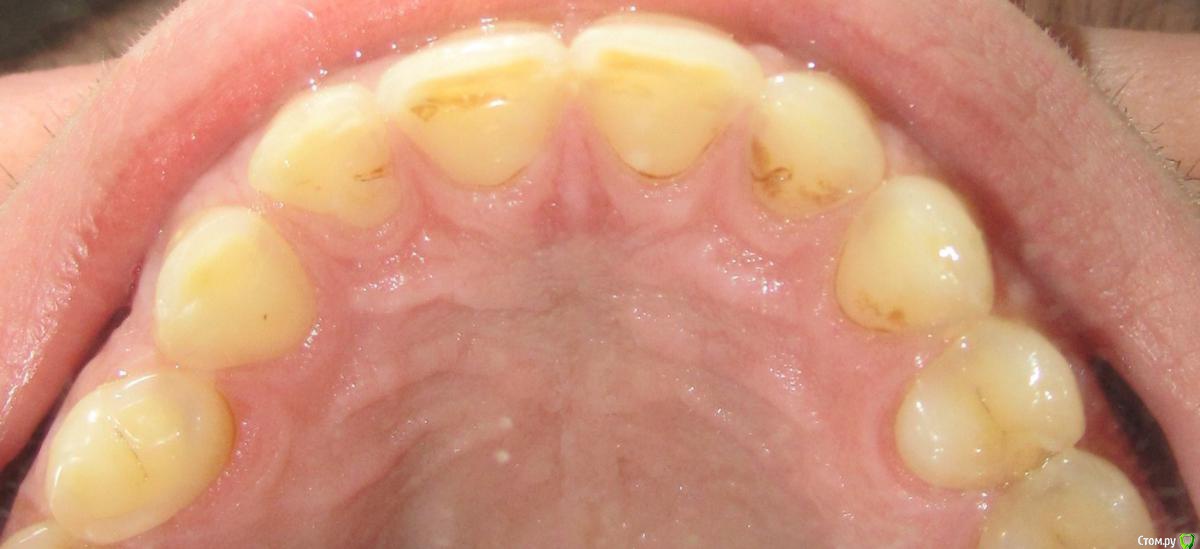

Coitus Interruptus Опубликовано 19 апреля, 2016 Поделиться Опубликовано 19 апреля, 2016 (изменено) Здравствуйте.Всё началось с того, как я догадался пить кока-колу, полоская ею рот, помногу и каждый день. Но в последние год-полтора начал ощущать что-то странное с задней стороны передних верхних зубов, и на просвет они стали тоньше, чётко видно линию изменения толщины, также заметны потемнения у их основания. Увеличилась чувствительность к температуре.Сходил к местному стоматологу не так давно, но он сказал лишь об относительно небольшом клиновидном дефекте, который у меня также имеет место быть. Про передние верхние зубки же- нет, у вас с ними всё почти нормально.Как к этому стоит относиться и что делать?В случае, если с этими зубами и правда всё не так нормально, есть способ их восстановить, или же скорее я останусь вообще без них? Изменено 19 апреля, 2016 пользователем Coitus Interruptus 1 Ссылка на комментарий

___49___ Опубликовано 19 апреля, 2016 Поделиться Опубликовано 19 апреля, 2016 Снимок не информативен. Ссылка на комментарий

___49___ Опубликовано 19 апреля, 2016 Поделиться Опубликовано 19 апреля, 2016 (изменено) попробуйте сфотографировать то - что у вас вызывает беспокойство . На первом фото кроме налета я ничего толком не увидел. Фото не высокого разрешения, не четкие , сделайте в разных ракурсах. Да и колу замените на что ни будь, например молоко . Изменено 19 апреля, 2016 пользователем ___49___ Ссылка на комментарий

shishok Опубликовано 21 апреля, 2016 Поделиться Опубликовано 21 апреля, 2016 Вылечите кариес на 24 и 25 зубе(если уже не вылечили).Что у Вас с прикусом:видны участки стираемости по режущему краю передних зубов. 2 Ссылка на комментарий